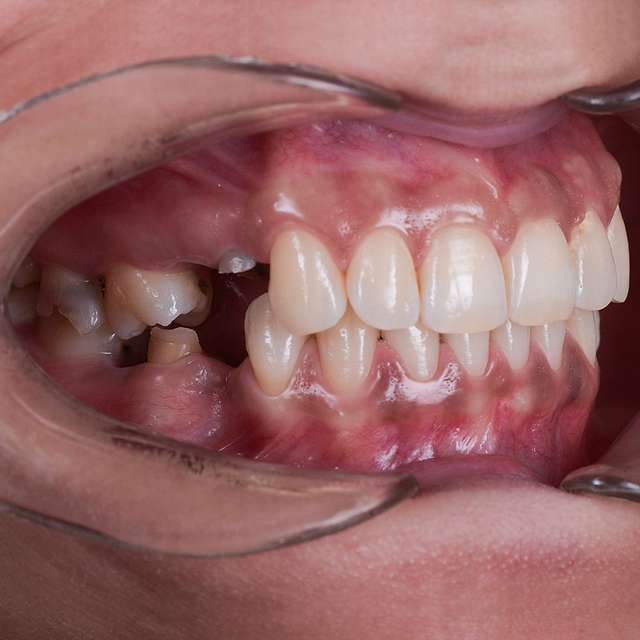

Guided surgery is safe and precise. A surgical guide is recommended in difficult or complex cases, to minimise risks and complications.

When implant therapy is performed with guided surgery, the surgery itself is simpler, and trauma is reduced especially for the soft-tissues. Overall we can achieve faster healing and better post-op comfort.